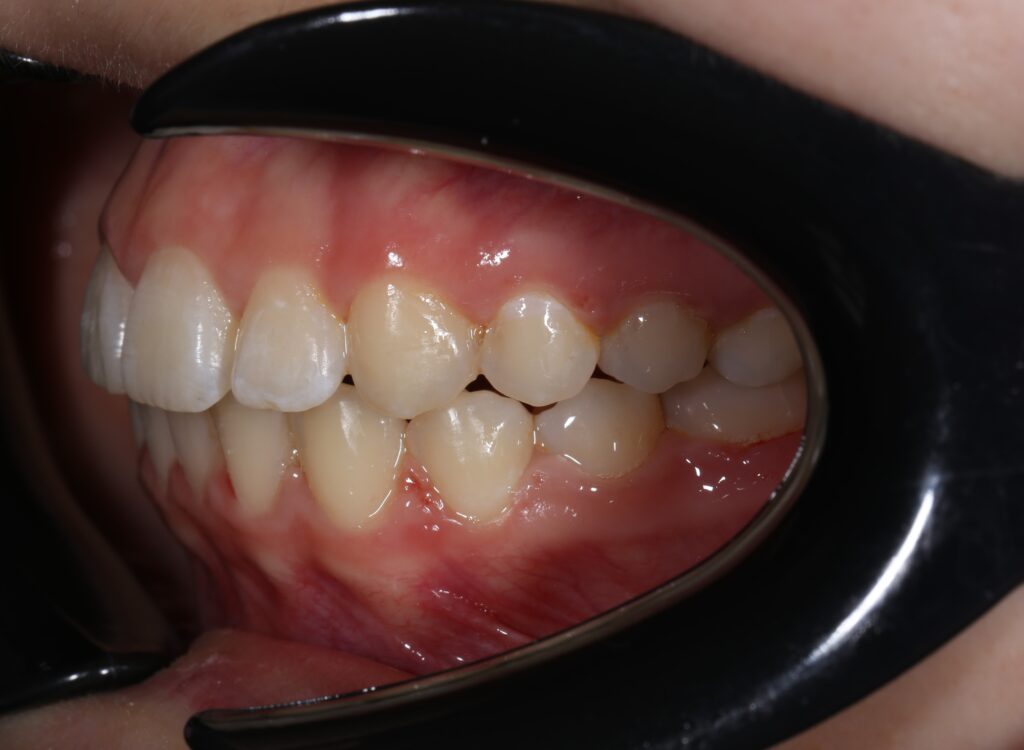

Ситуация до лечения

Жалобы: Пациентка обратилась с жалобами на неровное положение передних зубов.

Диагноз: дистальный прикус, сужение верхнего и нижнего зубных рядов, скученность фронтальной группы зубов на верхней и нижней челюсти.

пациент до лечения брекетами